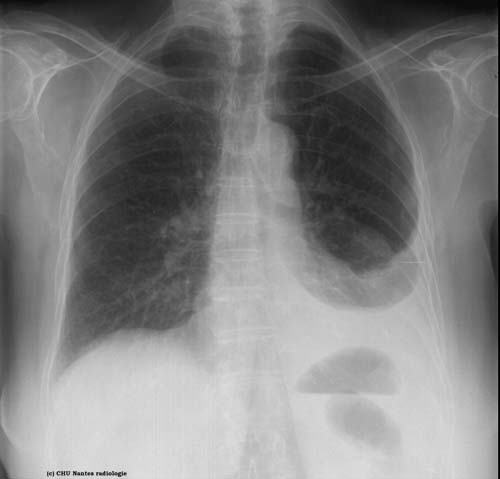

Epanchements liquidiens